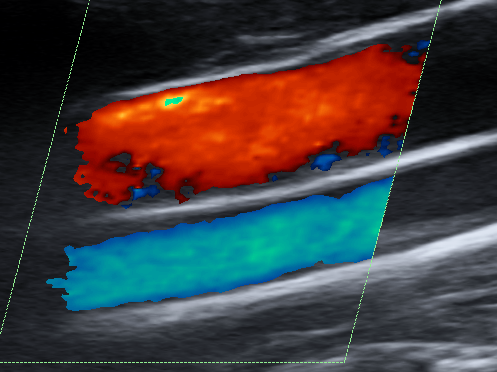

Doppler (carotid arteries. arteries and veins of the arms and legs) is a special ultrasound technique that evaluates blood flow through blood vessels.

Vessels that can be evaluated are in the neck (carotid arteries), major arteries in the abdomen as well as arteries and veins in the arms and legs.

Doppler studies are performed to rule out clots or thrombus in the veins as well as detect if there are any plaque or narrowing the arteries. Abnormal blood flow can be detected.